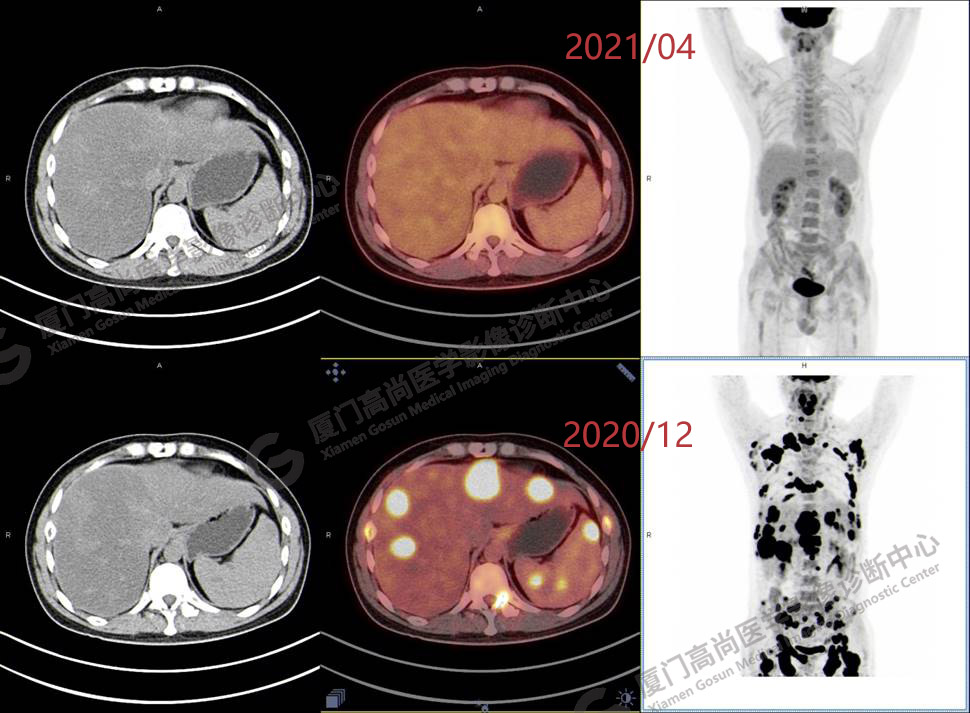

2020.12月本中心PET/CT示:全身多發(fā)腫大淋巴結(jié),代謝不同程度增高;肝臟多發(fā)稍高密度結(jié)節(jié)、脾臟多發(fā)稍低密度結(jié)節(jié),代謝異常增高;全身多發(fā)骨骼溶骨性骨質(zhì)破壞,代謝異常增高,胸2、腰1椎體病理性骨折,診斷為淋巴瘤。隨后,病理確診為彌漫大B細胞淋巴瘤。

患者化療4個療程后,于2021.04月返我中心復查,現(xiàn)患者本人已能自主行走,此次更是獨自一人來我中心復查PET/CT。檢查結(jié)果顯示:原全身多發(fā)病灶基本消失,且病灶代謝基本恢復正常。以下是患者PET/CT前后對比圖像:

PET/CT前后對比圖像1